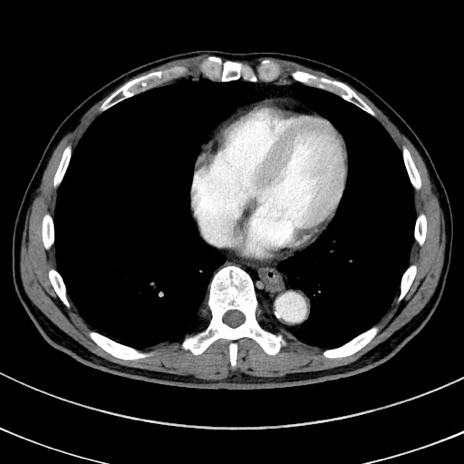

冠状断像

症例8(横断像)

【症例】 60歳代男性

【主訴】 黒色吐物

【現病歴】 4日前から嘔気自覚、2日前の朝食後にも嘔気あり、自分で手で嘔吐反射起こし嘔吐したところ血が混ざっていたため受診。

【既往歴】 5年前汎発性腹膜炎を伴う急性虫垂炎で手術、高血圧、前立腺肥大症、高脂血症

【身体所見】 腹部正中に手術癩痕あり 腹部平坦・軟圧痛なし膨満感あり

【データ】WBC 8400、CRP 4.54